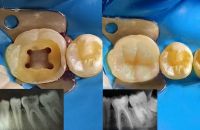

General Dentist with 4 + years of hands - on clinical experience in private and governmental clinics. Skilled in endodontics, restorative dentistry, pediatric cases, and fixed prosthodontics. Known for accurate diagnosis, efficient chairside work, and high patient satisfaction. DHA licensed and available for immediate work